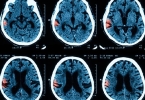

• 中风是突然的还是慢慢的

中风既可能突然发生也可能逐渐发展,具体表现与中风类型及血管病变程度有关。主要分为突发性脑梗死、渐进性脑缺血、短暂性脑缺血发作、脑出血、蛛网膜下腔出血五种情况。1、突发性脑梗死:突发性脑梗死占中风病例70% ...